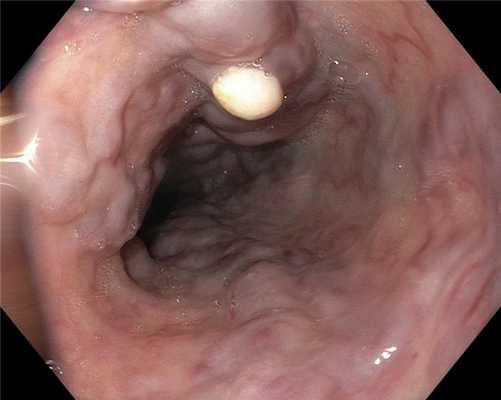

Рельеф слизистой оболочки терминального отдела подвздошной кишки. Гистологическое исследование от 18.02.2021 г. : Слизистая оболочка подвздошной кишки неравномерной толщины, с неравномерным расположением крипт. Ворсинки высокие, правильно ориентированы, выстланы зрелым эпителием кишечного типа. Имеются участки с низкими широкими ворсинками. В собственной пластинке умеренная лимфогистиоцитарная, эозинофильная инфильтрация, нейтрофильные гранулоциты отсутствуют. Межэпителиальные лимфоциты соответствуют норме. определяются участки с выраженной зрелой лимфоидной инфильтрацией и формированием лимфоидных фолликулов. В собственной пластине - выраженный фиброз. Заключение: Хронический илеит с участками атрофии и гиперплазией лимфоидной ткани, ассоциированной со слизистой оболочкой.

Нормальный рельеф слизистой оболочки терминального отдела подвздошной кишки